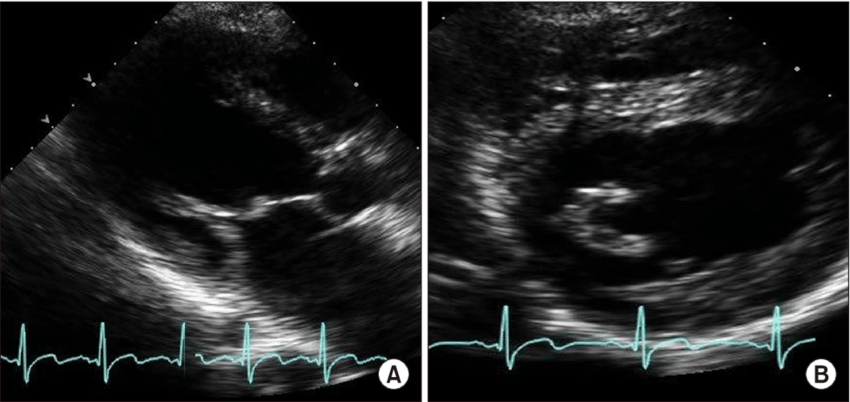

A

PArachute Papilary muscel. you can see just one papilary muscle

How well did you know this?

DX

Parachute-LIKE Mitral Valve. you can see in PSAX a big Anterolateral Papilary muscle and really small posterio papilary just beside

38